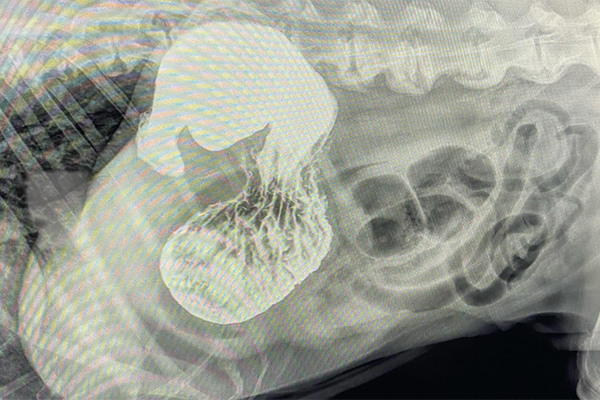

Barium Series

This procedure is a Contrast Study which means that we use a contrast dye that shows up on x-ray and highlights certain structures. Because some objects don’t show up on xray (plastic, fabric, toys, etc), this can help outline it or show us where the obstruction is as it can’t get past.

Our talented Registered Veterinary Technicians administer barium (the contrast liquid) in the mouth and then we take successive X-rays over the next few hours to watch its progress. The first X-ray is almost immediate to catch the outline of the esophagus while the last one may be hours later as it enters the colon .

Flip through the photos to see the progression of barium through the gastrointestinal tract: